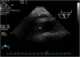

Ovarian cancer is a cancer that forms in or on an ovary. It results in abnormal cells that have the ability to invade or spread to other parts of the body. [Source: Wikipedia ]